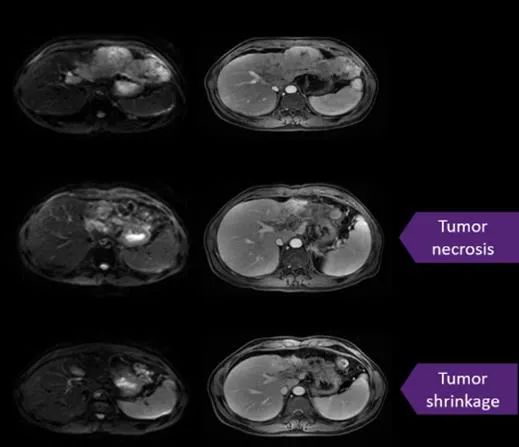

研究人员已经成功研发出了一种专门针对乙型肝炎病毒的特异性 T 细胞疗法--LioCyx-M。这是一种通过转染编码 HBV 抗原特异性 TCR 的 mRNA 的自体 T 细胞疗法,经过改造的T细胞能够精准识别杀伤表达 HBV 的肿瘤细胞,已在临床实验中用于治疗 HBV 相关肝癌和肝移植后复发性 HBV 相关肝癌。

“在两名肝移植患者身上成功进行了 20 多次 T 细胞输注,没有一名患者出现与治疗相关的不良反应,其中一名患者的肝癌远处转移瘤的肿瘤大小减小!”Thinesh Lee Krishnamoorthy博士说。

LioCyx-M在1 期研究 (NCT03899415)中用于治疗不可切除的乙型肝炎病毒 (HBV) 相关的肝细胞癌 (HCC)的卓越临床数据在2021年最佳肝癌峰会上震撼全场!

截至 2020 年 4 月 30 日,共8 名没有治愈性治疗选择的不可切除的 HBV 相关肝细胞癌 (HCC) 患者接受了LioCyx-M疗法。结果显示,在可评估的 7 名患者中,3 名患者病情稳定,其中1名患者肝脏肿瘤的大小显着减少30%以上,并维持了30个月!

更值得振奋的是,LioCyx-M疗法的中位总生存期为 33.57 个月,而 FDA 批准的一线药物索拉非尼的中位总生存期仅为 10.7 个月(Llovet 等,N英国医学杂志,2008),翻了3倍多!

此外,随访期为 47.9 个月,4名患者在数据截止时还活着。

研究人员兴奋的说,鉴于目前亚洲 80% 的 肝细胞癌病例与 HBV 相关,这种方法可能会在改善患有这种疾病的患者的生存率和生活质量方面取得重大突破。

好消息是,2021年12月,FDA授予乙型肝炎病毒 (HBV) 相关肝细胞癌 (HCC) 患者的潜在一流疗法 LioCyx-M004快速通道指定!有望加快在全球的上市步伐,我们期待这一显著改善 HBV相关肝细胞癌预后的创新疗法早日获批上市,造福更多患者。好消息是,这项国际前沿的TCR-T疗法正在新加披进行临床实验招募肝癌患者,除此之外,国内多项TCR-T疗法也正在进行临床实验,想寻求TCR-T细胞疗法及其他国内外治疗新技术帮助,且经济条件允许的情况下,患者可以先将病历提交至全球肿瘤医生网医学部进行初步评估。